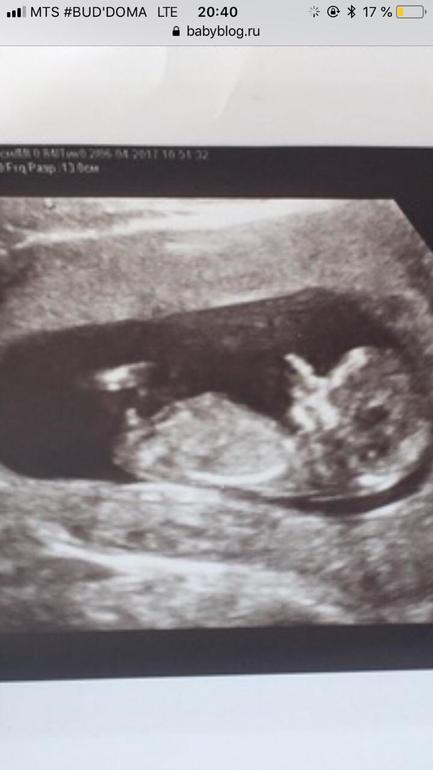

Смотрите фото прилагаю .

Это фото я кидала и многие предположили о нему девочку

( мне кажется тут пуповина между ног)